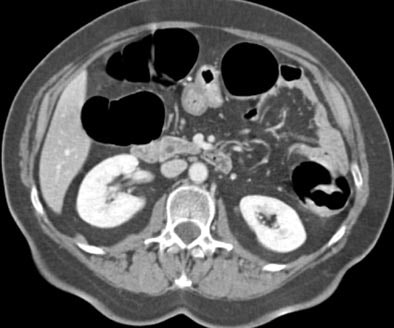

![]() |

| Transverse MDCT colonographic image after contrast material injection. An occlusive carcinoma 3 cm in diameter is identified within the descending colon. The lesion was correctly staged as T2 at CT. Image courtesy of Dr. Riccardo Iannaccone. |